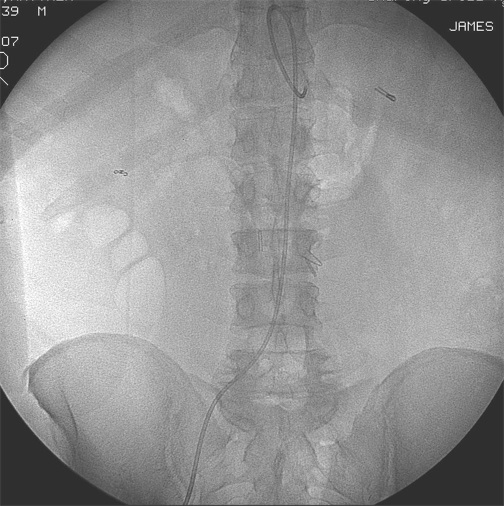

病例3